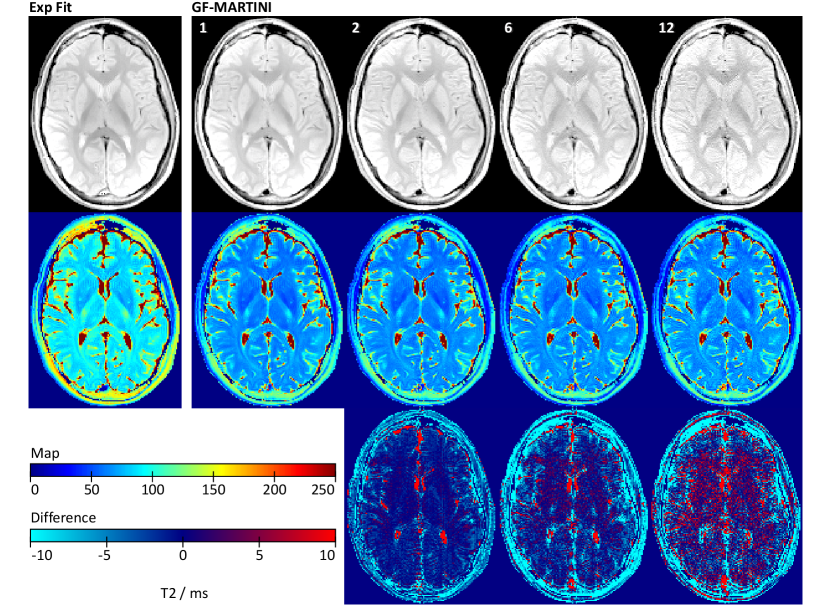

Corresponding results for a transverse section of the human brain are shown in Fig. 6.

Refer to caption

Figure 6: (Top) Spin-density and (center) color-coded T2 maps of the human brain obtained by (left) exponential fitting of fully sampled data and (right) GF-MARTINI reconstructions with validity mask for undersampling factors of 1, 2, 6 and 12. The corresponding measurement times were 12:54, 6:27, 2:09, and 1:05 min. Reconstruction was performed with the use of a previously measured T1 map, requiring an additional measurement time of 17:05 min. (Bottom) T2 difference maps with respect to the fully sampled reference.

Whereas a pixel-wise exponential fit of the fully sampled MSE data (first echo removed) again leads to a systematic T2 overestimation, the GF-MARTINI method presents with good accuracy for all undersampling factors. The most notable distortions are small vertical ghosts near the hemispheric fissure, which increase for higher undersampling factors. For the highest acceleration factor of 121212, also the spin-density map suffers from edge enhancement and blurring. A quantitative ROI analysis of T2 values in various brain tissues is summarized in Table III.